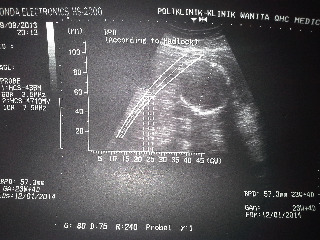

Babyku...